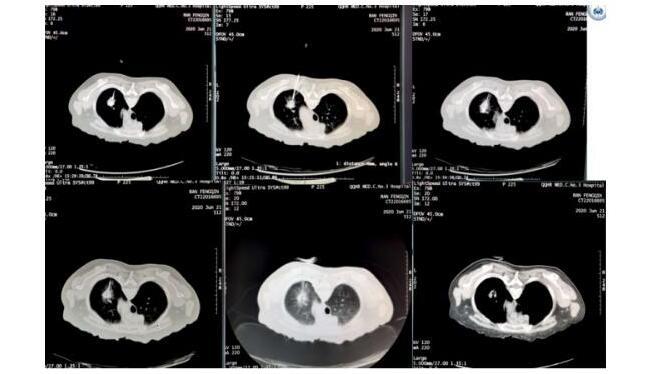

肺癌的支气管动脉灌注化疗与粒子植入

肺癌消融